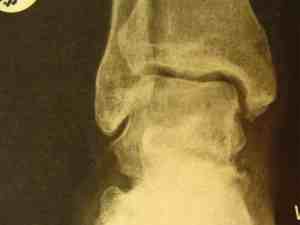

A forty year-old man fell about three metres, with immediate severe pain in the right foot. Within a short period the lower leg was oedematous and throbbing. He was unable to stand on the leg.

X-rays of the ankle were declared normal. Here they are.

Normal X-rays?

He was diagnosed with a bad sprain of the ankle, and put into a boot to limit movement.

Fractures in the ankle are notoriously difficult to see because of the overlapping structures. A scan revealed the partially healed fracture through the talus bone.

Worse, because of the disrupted blood supply to the talus, the main bone joining the leg to the foot is dying. A process called "avascular necrosis."

Can you see the great holes of dead bone in the talus? The fracture cut off the blood supply to the osteoblasts. It should have been pinned immediately.

How reliable are X-rays? Sometimes fractures can only be seen on a scan.